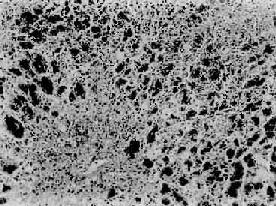

图10-36 病毒性肝炎 肝细胞点状坏死,坏死灶内有炎性细胞浸润 (4)溶解坏死(lytic necrosis)最多见,常由高度气球样变发展而来。此时胞核固缩、溶解、消失,最后细胞解体。重型肝炎时肝细胞的变性往往不明显,很快就发生此种坏死崩解。 2.炎细胞浸润肝炎时在汇管区或肝小叶内常有程度不等的炎性细胞浸润。浸润的炎细胞主要是淋巴细胞、单核细胞,有时也见少量浆细胞及中性粒细胞等。 3.间质反应性增生及肝细胞再生 (1)Kupffer细胞增生肥大:这是肝内单核吞噬细胞系统的炎性反应。增生的细胞呈梭形或多角形,胞浆丰富,突出于窦壁或自壁上脱入窦内成为游走的吞噬细胞。 (2)间叶细胞及纤维母细胞的增生:间叶细胞具有多向分化的潜能,存在于肝间质内,肝炎时可分化为组织细胞参与炎性细胞浸润。在反复发生严重坏死病例,由于大量纤维组织增生可发展成肝纤维化及肝硬变。 (3)肝细胞再生:肝细胞坏死时,邻近的肝细胞可通过直接或间接分裂而再生修复。在肝炎恢复期或慢性阶段则更为明显。再生的肝细胞体积较大,核大而染色较深,有的可有双核。慢性病例在汇管区尚可见细小胆管的增生。 上述肝炎基本病变中,肝细胞疏松化,气球样变,点状坏死及嗜酸性小体形成对于诊断普通型肝炎具有相对的特征性;而肝细胞的大片坏死、崩解则是重型肝炎的主要病变特征。 【临床病理类型】 各型肝炎病毒引起的肝炎其临床表现和病理变化基本相同。现在常用的分类是,在甲、乙、丙、丁、戊5型病毒病因分类之外,把病毒性肝炎从临床病理角度分为普通型及重型二大类。在普通型中分为急性及慢性两类。急性有急性无黄疸型及黄疸型;慢性有持续性(迁延性)及活动性。重型中又分为急性及亚急性两种。 1.急性(普通型)肝炎最常见。临床上又分为黄疸型和无黄疸型二种。我国以无黄疸型肝炎居多,其中多为乙型肝炎,一部分为丙型即过去所谓非甲非乙型的一部分。黄疸型肝炎的病变略重,病程较短,多见于甲型、丁型、戊型肝炎。两者病变基本相同,故一并叙述。 病变:广泛的肝细胞变性,以胞浆疏松化和气球样变最为普遍。坏死轻微,肝小叶内可有散在的点状坏死。嗜酸性小体的出现并非经常。由于点状坏死灶内的肝细胞索网状纤维支架保持完整而不塌陷,所以该处通过再生的肝细胞可完全恢复原来的结构和功能。汇管区及肝小叶内也有轻度的炎性细胞浸润。黄疸型者坏死灶稍多、稍重,毛细胆管管腔中有胆栓形成。 【临床病理联系】 由于肝细胞弥漫地变性肿胀,使肝体积增大,被膜紧张,为临床上肝大、肝区疼痛或压痛的原因。由于肝细胞坏死,释出细胞内的酶类入血,故血清谷丙转氨酶(SGPT)等升高,同时还可引起多种肝功能异常。肝细胞坏死较多时,胆红质的摄取、结合和分泌发生障碍,加之毛细胆管受压或有胆栓形成等则可引起黄疸。 结局:急性肝炎大多在半年内可逐渐恢复。点状坏死的肝细胞可完全再生修复。一部分病例(多为乙型、丙型肝炎)恢复较慢,需半年到一年,少数病例(约1%)可发展为慢性肝炎。极少数可恶化为重型肝炎。 2.慢性(普通型)肝炎病毒性肝炎病程持续在一年(国外定为半年)以上者即为慢性肝炎。其中乙型肝炎占绝大多数(80%),也有近年明确的丙型肝炎。按病程、肝功能情况、免疫状态及病变等的不同将慢性肝炎分为持续性(迁延性)和活动性(进展性)二种。 (1)慢性持续性肝炎(chronic persistent hepatitis,CPH):临床症状常较轻或仅有肝功能异常。镜下,肝细胞变性、坏死较急性时减轻,Kupffer细胞增生活跃,汇管区或小叶内慢性炎性细胞浸润明显。有时汇管区可因有少量结缔组织增生而变宽。肝小叶轮子廓清楚,小叶界板无破坏。肉眼观,肝体积增大,但表面平滑。此型肝炎一般发展缓慢,经过较好,大多数可以恢复,少数可转变为慢性活动性肝炎。 (2)慢性活动性肝炎(chuonic active hepatitis,CAH):此型肝炎病变较重,肝功能持续异常。镜下,肝细胞变性坏死更为广泛而严重。肝细胞坏死呈灶状或条带状,并具有以下二种特征。①小叶周边的肝细胞界板受到破坏,界板肝细胞呈灶状坏死、崩解,伴有炎性细胞浸润,称为碎片状坏死(piecemeal necrosis)(图10-37);②小叶中央静脉与汇管区之间或两个中央静脉之间出现肝细胞坏死带,称桥接坏死(bridging necrosis)。坏死区可出现肝细胞不规则再生。小叶周边部坏死区纤维组织增生呈星芒状向小叶内伸展,并与小叶内肝细胞坏死处网状纤维支架塌陷而胶原化的纤维条索相连接,形成纤维间隔而分割小叶结构。肉眼观,在肿大的肝表面,上述纤维化明显区呈不平滑颗粒状,质地较硬。此型常见于乙、丙型肝炎,除肝外,患者还有脾肿大等全身改变,如不及时治愈大都转入肝硬变。

图10-37 慢性活动性肝炎 肝细胞明显气球样变和嗜酸性变,小叶界板破坏呈现碎片状坏死,门管区见炎性细胞浸润 毛玻璃样肝细胞 多见于HBsAg携带者及慢性肝炎患者的肝组织。光镜下,HE染色切片上,此等肝细胞浆内充满嗜酸性细颗粒状物质,不透明似毛玻璃样故称毛玻璃样肝细胞(图10-38)。这些细胞内含大量HBsAg,电镜下呈线状或小管状积存在内质网池内。用免疫酶标法或免疫荧光法可呈HBsAg阳性反应。(图10-39)。